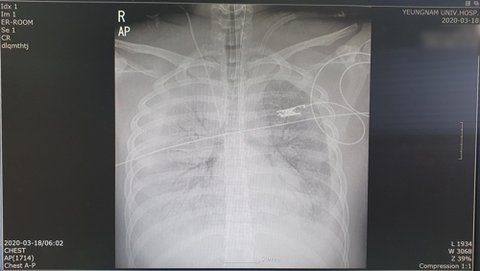

지난 13일부터 사망 당일인 18일까지 매일 찍은 엑스레이 사진은 점차 흰색으로 도배돼 일반인 눈으로도 폐가 제 기능을 할 수 없는 상황임을 알아챌 수 있다.

AST는 16일 467로 치솟아 17일 546, 사망 당일인 18일에는 898까지 올라갔다. ALT도 17일 139, 18일 187로 정상 범위를 급격하게 초과했다.

진료기록과 폐CT·엑스레이를 확인한 대구지역 내과 전문의 A씨는 "엑스레이상 초반에는 오른쪽 폐 상태가 나빴는데 점점 증상이 양쪽으로 심해졌다"며 "처음 방문한 병원에서 침윤 증세, 즉 폐렴 소견을 낸 것으로 보아 첫 번째 병원에 방문하기 전부터 몸 상태가 좋지 않았을 수도 있다는 생각이 든다"고 말했다.

그는 "세균성 폐렴일 경우 백혈구 수치가 올라가지만, 바이러스성 폐렴은 그렇지 않다"며 "정군의 경우 16일 오전 10시 32분까지 7.74로 정상 범주이던 백혈구 수치가 같은 날 오후 6시 58분에는 11.55로 올라갔다"고 지적했다.